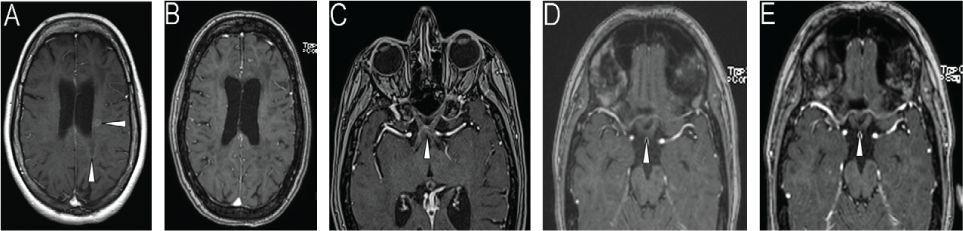

Serial T1-weighted brain magnetic resonance images of the patient after gadolinium administration

A 33-year-old woman was diagnosed at age 16 years as having relapsing-remitting MS based on clinical and magnetic resonance imaging (MRI) criteria. She had been taking several different disease-modifying therapies, including interferon beta-1a, interferon beta-1b, and natalizumab. Natalizumab use was discontinued due to a positive JC virus titer (JCV index, 0.73). Four months later she was admitted to the hospital for a multifocal relapse involving dysarthria, declining mobility, and cognitive impairment for several weeks. Examination was notable for trouble with following commands, word-finding difficulty, dysarthria, and paraparesis. The MRI performed before alemtuzumab use showed several new T2 lesions and areas of gadolinium enhancement (Figure 1A and Figure S1 [A1 and A2], which is published in the online version of this article at ijmsc.org). She received her first alemtuzumab infusion during the hospitalization. The preinfusion lymphocyte count was 1.24 × 109/L (reference range, 1.50–7.50 × 109/L). Approximately 6 weeks after hospitalization she was referred to our clinic, where her examination findings returned to baseline levels (visual acuity: 20/30 OD and 20/20 OS, no dysarthria or word-finding difficulty, and ambulatory without assistance). Follow-up brain MRI 3 months later showed no new lesions and resolution of the gadolinium-enhancing lesions (Figure 1B and Figure S1 [B1 and B2]). Laboratory investigations showed an elevated thyrotropin level (5.28 mIU/L) and a lymphocyte count of 0.87 × 109/L.

One month later the patient presented with bilateral vision loss and altered gait (ataxia and began using a walker). Examination showed a visual acuity of 20/100 – 1 at 1 ft OD and finger counting (one of three responses correct) OS along with worsening paraparesis. Urgent MRI showed multiple new gadolinium-enhancing lesions, including in the optic chiasm and nerves (Figure 1C and Figure S1 [C1–C4]), deep white matter, posterior fossa, and upper cervical spinal cord. Treatment was initiated with 5 days of intravenous methylprednisolone (Solu-Medrol; Pfizer, New York, NY) (1000 mg/d), followed by a 14-day prednisone taper. Her lymphocyte count was 0.77 × 109/L, and flow cytometry showed a normal number of B cells (0.33 × 109/L; reference range, 0.079–0.36 × 109/L) and a decreased absolute T-cell count (0.089 × 109/L; reference range, 0.53–2.19 × 109/L). Seven days later her gait improved (narrowed stance and ability to walk a few steps without assistance), as did her visual acuity (20/80 OD and 20/160 OS). Repeated brain MRI 7 weeks later showed reduced gadolinium enhancement of the optic chiasm and fewer gadolinium-enhancing lesions (not shown). Shortly after MRI, the patient began to develop worsening cognitive decline and vision. She was treated with 5 days of oral prednisone (1250 mg/d) followed by hospitalization with 3 days of intravenous Solu-Medrol (1000 mg/d). Plasma exchange was initiated 4 weeks later because of incomplete improvement of neurologic status. The patient received nine plasma exchanges over 6 weeks. Prednisone therapy was maintained at 80 mg/d during plasma exchange. After five exchanges, her visual acuity improved to 20/50 OD and 20/40 OS, and her cognition and gait returned to baseline status (narrow-based gait, walking without assistance). Prednisone use was tapered to 30 mg/d, and brain MRI approximately 2 months (Figure 1D and Figure S1 [D1–D5]) and 3 months (Figure 1E and Figure S1 [E1–E5]) later showed resolution of all gadolinium-enhancing lesions and no new lesions. Five weeks later, her visual acuity was 20/25 OD and 20/40 OS.